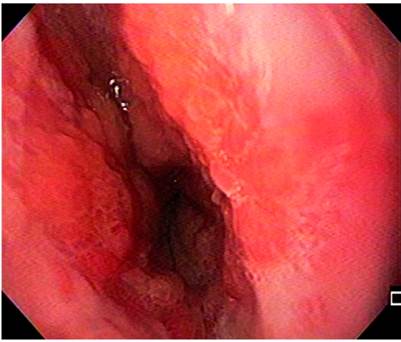

Por la disfagia reciente, se indicaron diversos estudios. En primer lugar, se realizó una radiografía de las vías digestivas altas, la cual evidenció un aumento del diámetro del esófago, reflujo severo y la alteración del peristaltismo con ondas terciarias (Figura 2). Además, se efectuó una EGD, que mostró una esofagitis de grado D (según la clasificación de los Ángeles), un pólipo hiperplásico, una hernia hiatal pequeña, antro con gastritis folicular y un duodeno normal (Figura 3).

Entre tanto, las biopsias mostraron compatibilidad con esofagitis péptica aguda severa, extensa ulceración y tejido de granulación, mientras que en la manometría esofágica de alta resolución se observó hipotonía del esfínter esofágico inferior y aperistalsis esofágica, según la clasificación de Chicago 3 (Figura 4).